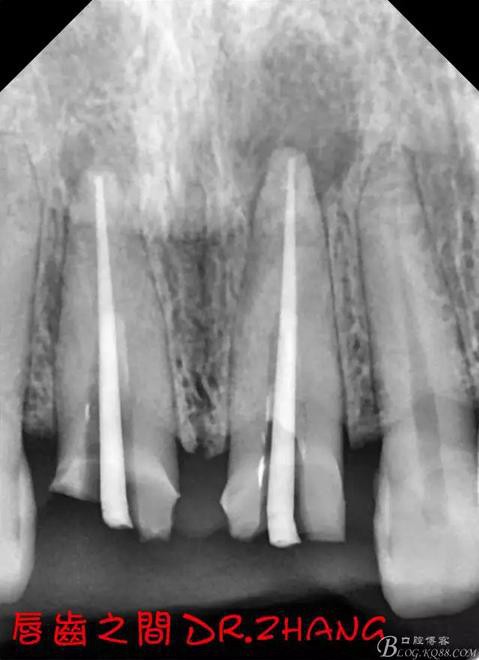

復(fù)診:腫脹明顯消失 患者自訴感覺良好 溝通后決定拆除11 21兩顆烤瓷冠后重新修復(fù) 去冠器直接去冠 去除11根管內(nèi)的充填物 15#K銼疏通根管 11 21根長均為16MM平斷面 薩尼S3系統(tǒng)機擴至2S 期間不斷用氯己定和鹽水交替沖洗 吸潮紙尖干燥根管后06 25#試尖

思博安熱牙膠系統(tǒng)根充 燙斷至根尖三分之一處后纖維樁恢復(fù)牙體組織

牙體預(yù)備后 硅橡膠取模 臨時牙恢復(fù)形態(tài)

復(fù)診:臨時牙良好 患者自訴無不適癥狀 去除臨時修復(fù)體 排齦 清理牙面 試戴全瓷修復(fù)體后粘結(jié) 常規(guī)醫(yī)囑 不適隨診